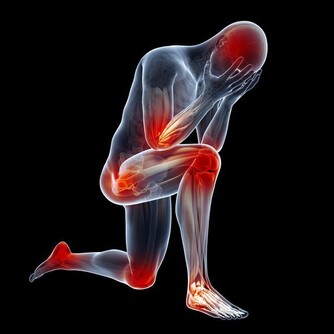

有發疹、劇烈頭痛、關節痛、痙攣症狀。

身體這些狀況就需要注意了

第一,胳膊、腿麻木、刺痛,精神紊亂、暈眩,說話打顫、語無倫次。尤其是面部或者身體一側出現上述情況,就可能是中風,也就是腦卒中的前兆,預示向大腦供氧的動脈堵塞或者破裂。如果是大動脈出問題,大腦中很大一部分就會受到影響,進而導致半身麻痺,同時失去講話等功能。如果是小血管出問題,胳膊或腿會麻木。出現上述症狀應立刻就醫。一般說來,血栓發生三小時內是治療的最佳時機。

第四,腿肚子酸痛、胸痛、氣短、咳血。這些是危險的腿部血栓形成前兆。久坐之後最易發生,手術之後長時間臥床,也會出現這種症狀。人人都可能得這種病,坐臥時間久了,血液淤積在腿部,腿部出現血栓,小腿肚子腫疼,此時如果突然出現胸痛或者氣短,說明血栓可能已經脫落並通過血液進入肺部。那可是萬分危險,要立刻去醫院。